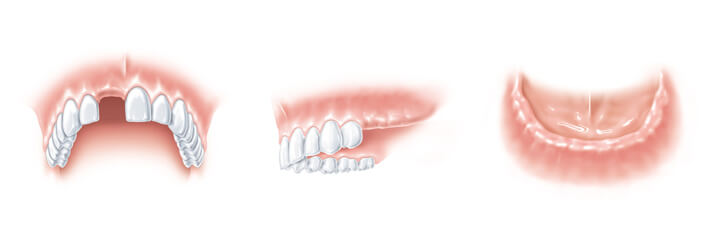

Mit schönen Zähnen fällt nicht nur ein positives Lächeln sehr viel leichter; Zähne sind ein wichtiger Bestandteil der Lebensqualität. Die Ursachen für Zahnverlust sind sehr unterschiedlich: Statistisch gesehen, gehen heutzutage mehr als 50%

aller Zähne im Erwachsenenalter durch Parodontose verloren, zu einem früheren Zeitpunkt ist meistens Karies die Ursache. Darüber hinaus gibt es auch Lücken durch Unfälle oder weil manche Zähne erst gar nicht gewachsen sind. Entstehende

Zahnlücken sollten möglichst bald geschlossen werden, um gefährliche Wanderungen der Nachbar- und Gegenzähne sowie den folgenden Knochenabbau zu vermeiden. Kommt es zum Zahnverlust, haben viele Menschen Probleme beim Sprechen, beim Essen

oder beim unbeschwerten Lachen – entweder durch die Zahnlücken oder wegen eines schlecht sitzenden oder kosmetisch unschönen Zahnersatzes. Herausnehmbare Prothesen haben erhebliche Nachteile. Oft ist die Kaufunktion eingeschränkt, die

Aussprache gestört und ein entspanntes Essen ist nur mit Komplikationen möglich. Wenn kleinere Zahnlücken oder Einzelzahnlücken zu schließen sind, so werden oft die gesunden Nachbarzähne beschliffen. Die moderne, ästhetische Zahnmedizin

bietet durch Implantate eine bewährte und komfortable Alternative zum normalen Zahnersatz.

Je nach individueller Aufgabenstellung beim Patienten unterscheidet sich die Einzelzahnlücke von der Situation, dass mehrere Zähne fehlen (Schaltlücke oder Freiendsituation). Daneben gibt es noch das reduzierte Restgebiss, bei dem die

verbliebenen Zähne für einen Zahnersatz nicht mehr genug Halt bieten. Wenn ein ganzer Kiefer zahnlos ist, kann mittels Zahnimplantaten eine Prothese sicher befestigt werden. Der wichtigste Vorteil eines Zahnimplantates besteht im Erhalt von

natürlichen Strukturen und bietet somit Schutz vor einem Knochenabbau.